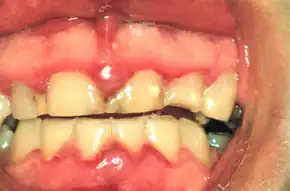

| A fairly mild presentation of acute necrotizing ulcerative gingivitis at the typical site on the gums of the anterior mandibular teeth. | |

In the early stages some affected people may complain of a feeling of tightness around the teeth.[3] Three signs/symptoms must be present to diagnose this condition:[3]

- Severe gum pain.[4]

- Profuse gum bleeding that requires little or no provocation.[3]

- Interdental papillae are ulcerated with dead tissue.[4] The papillary necrosis of NUG has been described as "punched out".[3]